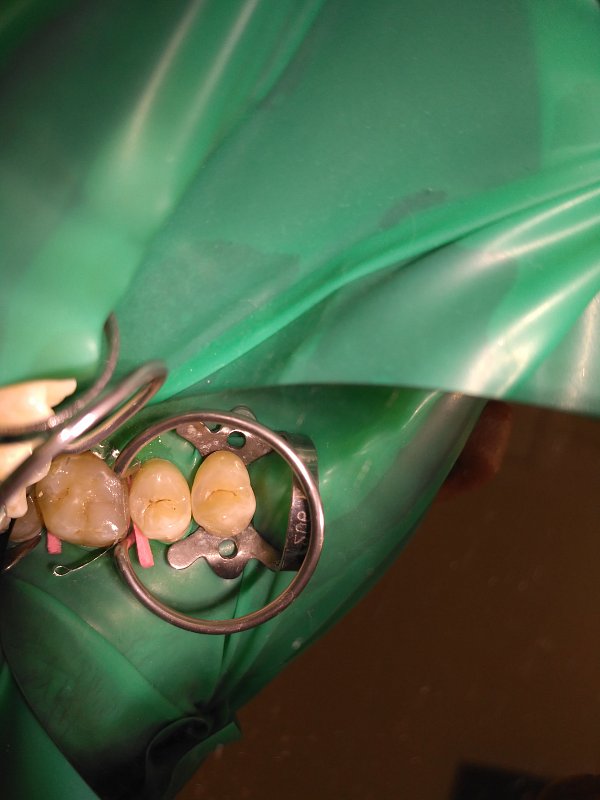

Пациент обратился с жалобами на кариес зубов.

Исходное состояние: Зубы под реставрациями неудовлетворяющими клиническим требованиям

Выполнена реставрация накладками из прессованной керамики.